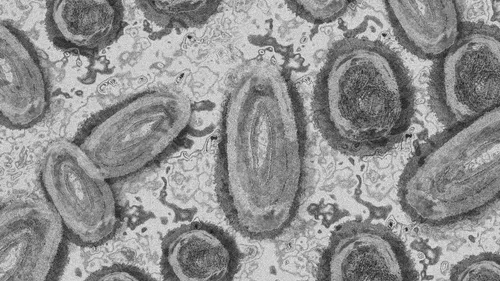

En France, 1 567 cas ont été recensés depuis mai.